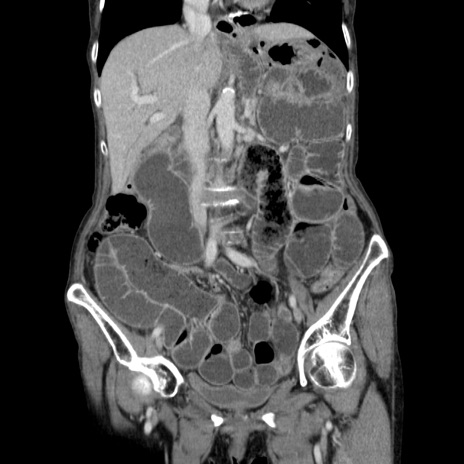

横断像

【症例】80歳代女性

【主訴】胸のつかえ感

【現病歴】約9時間前に食後から胸のつかえた感じあり、嘔吐あり、来院。

【既往歴】胃癌(全摘)、胆摘、虫垂炎

【身体所見】心窩部に圧痛あり、反跳痛なし。

【データ】WBC 5700、CRP 0.05